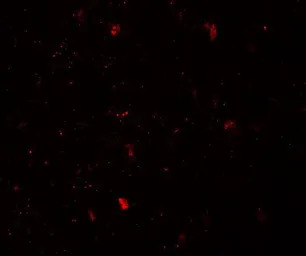

IHC-P analysis of mouse brain tissue using GTX31508 LMX1B antibody.

Working concentration : 5 μg/ml